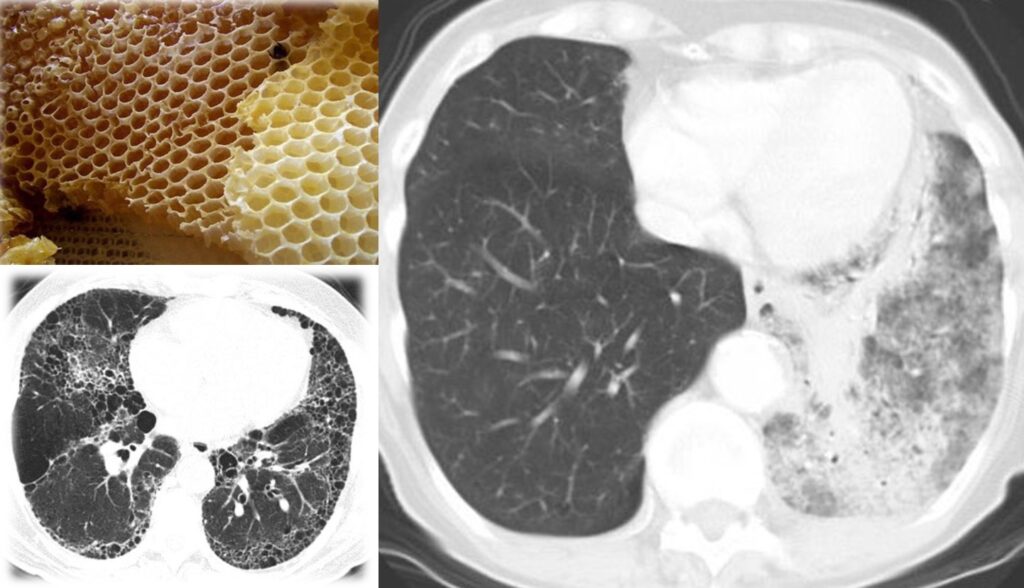

TC del torace ad alta risoluzione (HR) La Tomografia Computerizzata ad Alta Risoluzione (TC HR) rappresenta oggi il gold standard per lo studio delle malattie